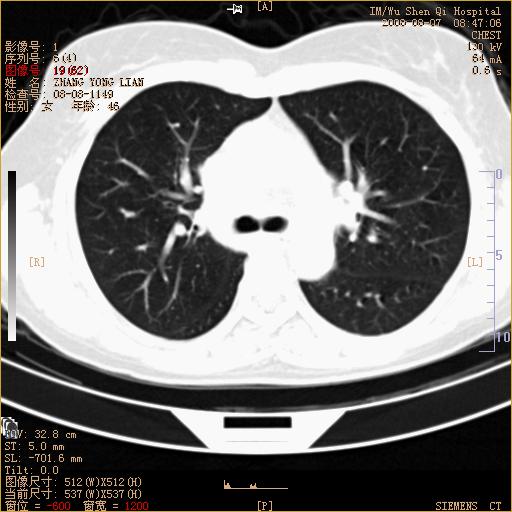

标题: CT15050:女,46岁,咳嗽胸痛一月余 [打印本页]

纵隔窗没发全,左下肺近胸膜处结节。有长毛刺,纵隔淋巴结增大,不排除恶性病变。

考虑肺癌

考虑左肺下叶后基底段周围型肺癌伴纵隔淋巴结转移可能性大。

左下肺ca并纵隔及左肺门区淋巴结转移。

1)考虑左肺下叶后基底段周围型肺癌伴纵隔淋巴结转移。2)脾内低密度灶,性质待定;不排除转移瘤可能。

考虑左肺下叶后基底段周围型肺癌伴纵隔及肺门淋巴转移。